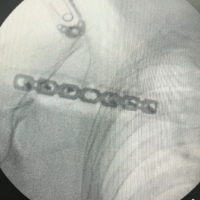

Under general anesthesia in beach chair position, a 5–7 cm vertical (“bra-strap”) incision was made from the tip of the coracoid process to anterosuperior aspect of the lateral third of the clavicle. Medial and lateral flaps were developed. The deltotrapezial fascia was then incised perpendicular to the skin incision and released from the clavicle. The fracture ends and coracoid was exposed. Dissection medial to the coracoid was avoided to prevent inadvertent damage to neurovascular structures. A tunnel was made at the coracoid base centrally about 1.5 cm from its tip using a 2.5 mm drill bit. Another bony tunnel was made in the clavicle just above the coracoid slightly anterior to the midline. Then, an EndoButton loaded with ethibond suture no. 5 was passed under the coracoid and the clavicle tunnel in a retrograde fashion so that the EndoButton flipped on the undersurface of the coracoid and two ends of the suture come out of the clavicle which were later tied to the distal clavicle plate. The fracture ends were then reduced and fixed with anatomically pre-contoured locking distal clavicle plate, as shown in Fig. 1.

Figure 1: Clavicular fracture fixation done with anatomically pre-contoured plate and ligamentous reconstruction done with tunneled suspensory device (EndoButton).

Figure 2: Immediate post-operative radiograph of the unstable lateral end clavicle fixed with our surgical technique.

Proper hemostasis was achieved and wound was closed in layers. No drain was applied. The arm was immobilized in an arm pouch. Immediate post-operative radiograph was done (Fig. 2).